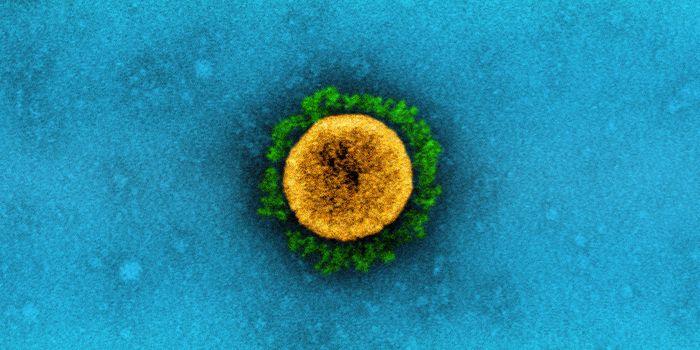

JUL 05, 2020Cell & Molecular BiologyThe pandemic virus SARS-CoV-2 enters the body through the respiratory system to cause the illness COVID-19. But we know ...

MAR 18, 2020MicrobiologySARS-CoV-2 is a coronavirus that causes an illness called COVID-19. There are now well over 210,000 confirmed cases worl ...

APR 06, 2020Genetics & GenomicsSARS-CoV-2 is the name for the pandemic coronavirus that causes the illness COVID-19, which affects people in extremely ...

APR 26, 2020Cell & Molecular BiologyThis work may help explain why the virus is so easy to transmit.